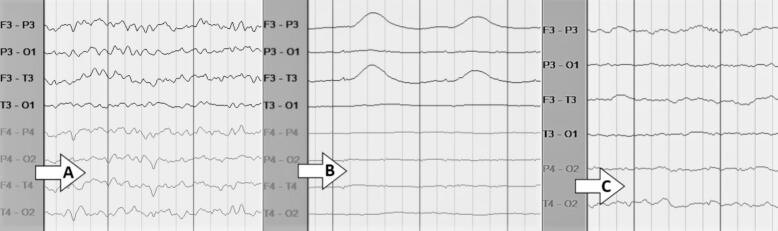

IONM and clinical data from 273 patients who underwent craniotomy for aneurysm clipping from 2019 until 2021 were retrospectively reviewed. Significant IONM changes and POD were respectively evaluated based on visual review of data and clinical documentation. POD was assessed multiple times in the ICU using the Intensive Care Delirium Screening Checklist (ICDSC).

Of the 273 patients undergoing craniotomy with IONM, 83 had POD (30.4 %). Significant IONM changes were noted in 42 patients, of which 19 patients had POD (45.2 %). In contrast, 231 patients had no IONM changes during surgery, of which 64 (27.7 %) patients had POD. Multivariable analysis showed that significant IONM changes were associated with POD, OR: 2.09 (95 % CI 1.01–4.43, p-value: 0.046). Additionally, somatosensory evoked potentials (SSEP) changes were significantly associated with POD (p-value: 0.044).

Significant IONM changes are associated with an increased risk of POD in patients undergoing craniotomy for aneurysm clipping. Our findings offer a strong basis for future research and analysis of EEG and SSEP monitoring to detect and possibly prevent POD.